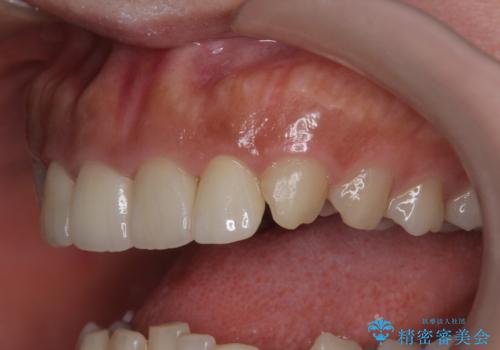

- 他院で昨年治療したセラミッククラウンが欠け、審美性の改善を求めて来院されました。

噛み合わせからクラウンが欠けやすい状態だったので、欠けにくく強度に優れるフルジルコニアクラウンで審美性を改善します。

フルジルコニアクラウンは若干透明感に劣る反面、強度に優れ大きな力のかかる部位に有効な補綴方法です。